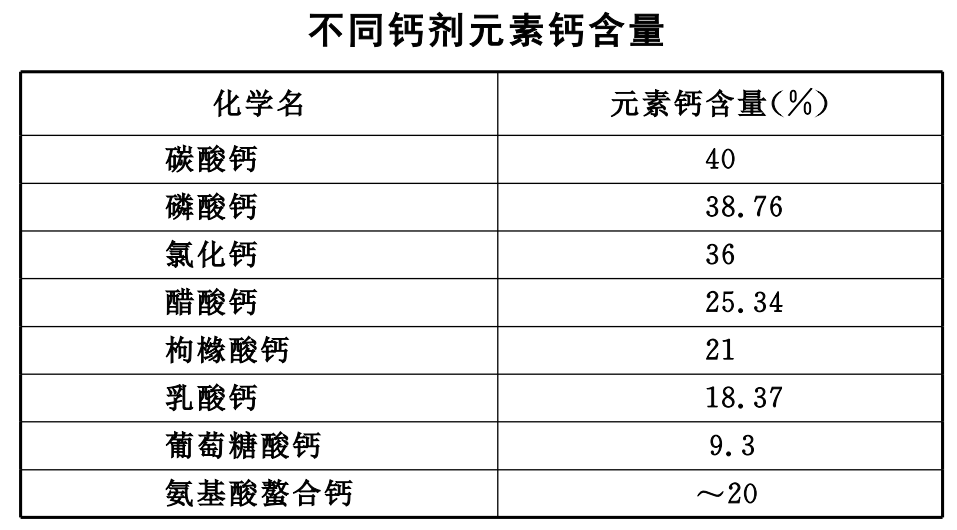

1、钙制剂:

骨质疏松患者的基础治疗用药,通过补钙,达到改善骨吸收和骨代谢的平衡。

按照我国老年人每日需钙量 1000~1200 mg 计算,除每日饮食供给 500~600 mg 外,还应补充钙 500~600 mg/d。

常用钙制剂分无机钙和有机钙两类,无机钙含钙高,作用快,但对胃刺激性大。有机钙含量低,吸收较好,刺激性较小。

①无机钙:

a. 氯化钙:每日 400~800 mg 饭后服。

b. 碳酸钙:每次 0.5~1.0 g;2~3 次/d。该药在口服钙制剂中作为首选,含钙量高,吸收率好,与牛奶钙吸收率相同,价廉,服用方便。

②有机钙:

a. 葡萄糖酸钙:0.4~2.0 g 静注;口服每次 1.5 g;3 次/d。

b. 乳酸钙:每次服 1.5 g;3 次/d。

c. 门冬氨酸钙:每次服 0.2~0.4 g;3 次/d。

③活性钙:是一种可溶性钙盐,生物利用度高。

④钙尔奇 D:每片含元素钙 600 mg,含维生素 D 约 125 U,钙的吸收率较高,每天服 1~2 片,即可满足人体对钙的需求。

由于人体不能吸收和储存过量的钙,且钙的吸收率与服用钙剂量的对数成正比,因此,补钙应注意不间断地长期给予均衡剂量,分多次服用,效果较好。